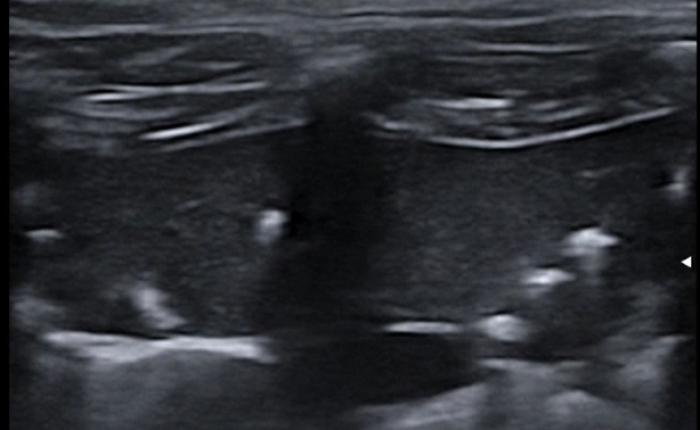

Comenzaremos posicionando el transductor perpendicular a las costillas en uno de los espacios intercostales, pudiendo evaluar al menos el espacio entre dos costillas, la línea PP y no más de 2-3 cm de profundidad de campo (Figura 1A-B).